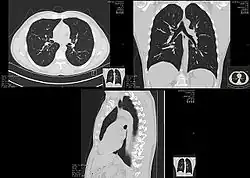

CT scan of the thorax. The axial slice (right) is the image that corresponds to number 2/33 on the coronal slice (left).

Spinning tube, commonly called spiral CT, or helical CT, is an imaging technique in which an entire X-ray tube is spun around the central axis of the area being scanned. These are the dominant type of scanners on the market because they have been manufactured longer and offer a lower cost of production and purchase. The main limitation of this type of CT is the bulk and inertia of the equipment (X-ray tube assembly and detector array on the opposite side of the circle) which limits the speed at which the equipment can spin. Some designs use two X-ray sources and detector arrays offset by an angle, as a technique to improve temporal resolution.[8][9]